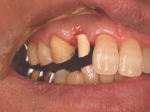

片側2歯欠損 主訴-入れ歯を使ってみたが違和感強くてダメ。固定のものにしたい。術前下顎口腔内(鏡像)

術後、左下奥2本インプラント(鏡像)